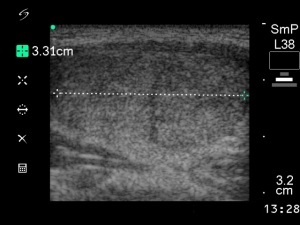

First session of sclerotherapy (1st row of images)

Clinical presentation: a 27-year-old woman was referred for evaluation of a multinodular goiter. The lesion in the left lobe has increased in the past two years and caused neck discomfort.

Palpation: a not firm nodule in the left lobe.

Functional state: euthyroidism with TSH 0.93 mIU/L, FT4 14,3 pM/L.

Ultrasonography: the thyroids were echonormal. There was a small lesion with a maximal diameter of 7 mm in the right lobe and a larger nodule in the left lobe. Both were echonormal.

Aspiration cytology resulted in benign colloid goiter.

We suggested surgery because of the compression signs. The patient told us that she is a cook in a seafarer and she has the opportunity to miss from the work only for a couple of weeks in the subsequent years. We advised ethanol sclerotherapy. Six sessions of ethanol was given. A total amount of 13.7 mL ethanol was administered in six session in 5 weeks.